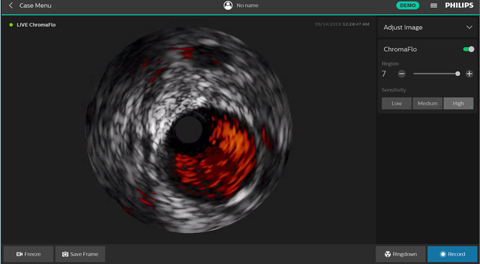

ChromaFlo provides easy assessment of stent apposition, lumen size and more by highlighting blood flow red at the touch of a button. ChromaFlo is available on Philips imaging systems.

Designed to make lumen size and stent apposition instantly recognizable and help identify branches, dissections, thrombus, and plaque distribution in bifurcations. ChromaFlo highlights blood flow red to identify:

No flushing and no special procedures are required during imaging. Simply activate ChromaFlo with a click.

ChromaFlo works with the Philips Eagle Eye Platinum digital IVUS catheters.